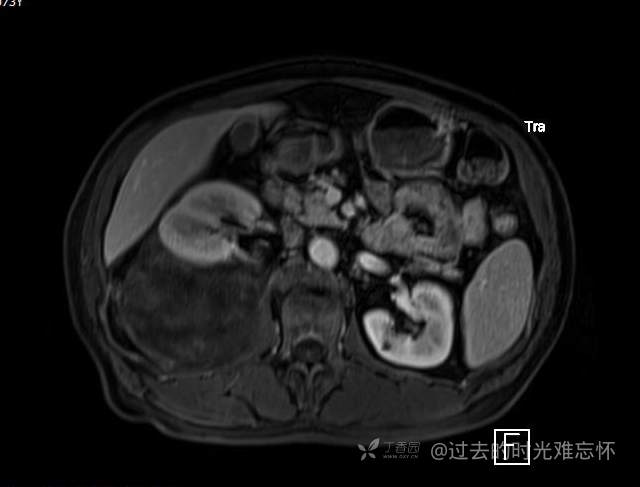

患者性别:男

患者年龄:73岁

主诉:咳嗽1月余。曾有血尿一次。后背部酸痛不适1-2年左右,无明显消瘦。

辅助检查:CT MRI

临床诊断:占位

治疗经过:手术

ADC DWI

黏液样脂肪肉瘤 (12)